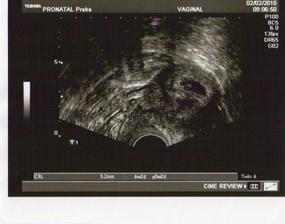

25. září čekáme miminko

Po jednou neúspěchu teď věříme v úspěch. Držte palce!